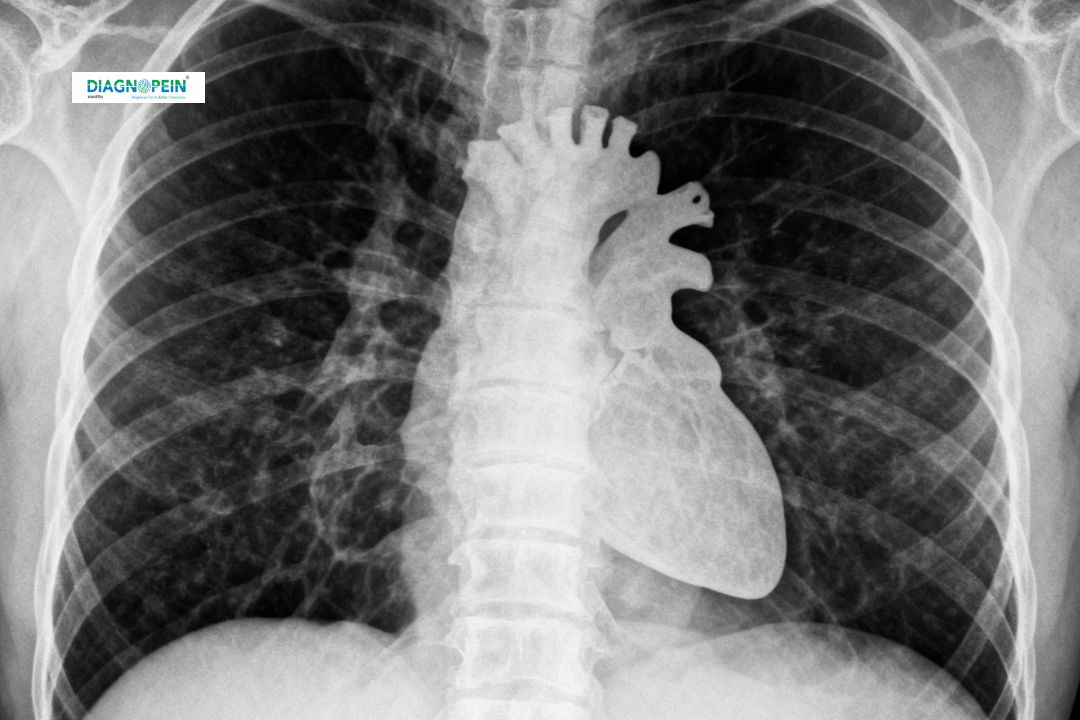

An X-Ray Chest AP (Anteroposterior) View is a vital imaging test that helps evaluate the lungs, heart, chest wall, and nearby structures. At Diagnopein in Karad, we offer advanced digital X-ray facilities ensuring quick, accurate, and safe imaging results for both routine and emergency cases.

This diagnostic test is especially useful when patients cannot stand for a standard PA (Posteroanterior) view, such as those who are bedridden or critically ill. The X-Ray Chest AP View helps physicians identify a wide range of chest and lung conditions, including infections, asthma, heart enlargement, fluid accumulation, or trauma-related abnormalities.

The X-Ray Chest AP View is one of the most commonly requested imaging tests because it provides a rapid and detailed look at the internal chest organs. It plays an essential role in detecting and monitoring health conditions such as:

1. Pneumonia, bronchitis, or tuberculosis

2. Congestive heart failure or cardiomegaly

3. Lung infections and tumors

4. Pleural effusion (fluid around the lungs)

5. Chest injuries or rib fractures

At Diagnopein, we prioritize patient comfort and accuracy. During the X-Ray Chest AP View, the patient is typically positioned lying on an examination table or sitting upright. The X-ray beam passes from the front (anterior) of the chest to the back (posterior), capturing an image of the heart, lungs, ribs, and diaphragm.

Chest X-Ray AP View helps evaluate several diagnostic parameters including:

1. Lung field clarity and air patterns

2. Size and contour of the heart

3. Presence of pleural effusion or fluid accumulation

4. Rib cage integrity and bone abnormalities

5. Position of medical devices like catheters or pacemakers